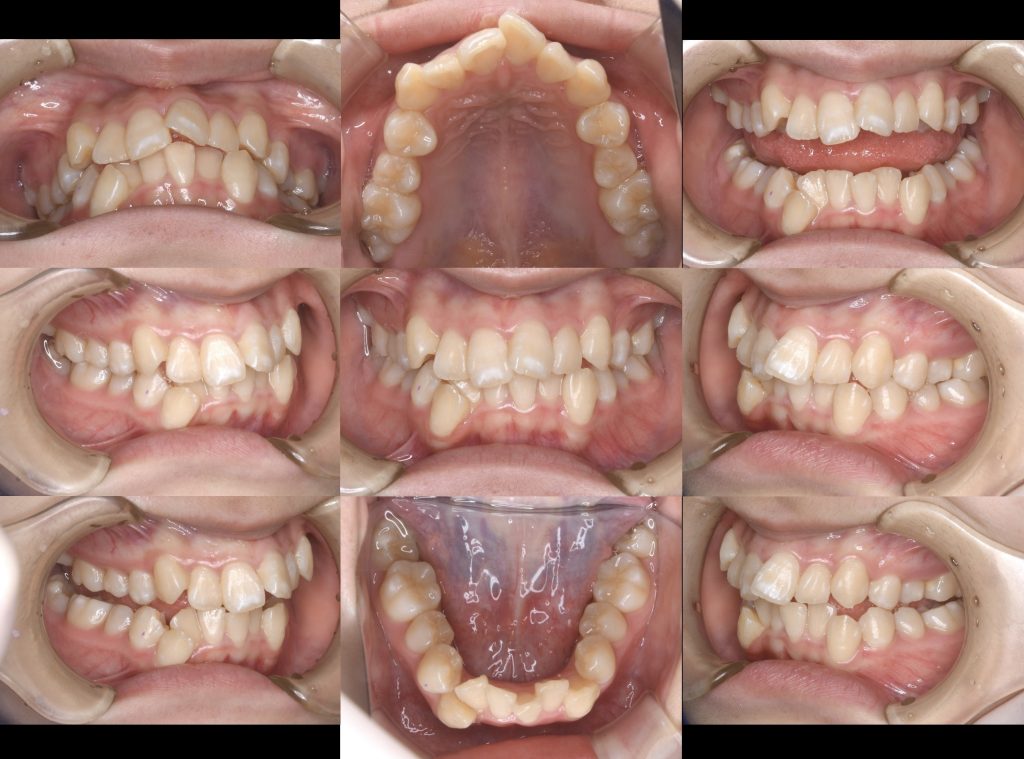

下記の症例は歯列不正(叢生)に対して、第一小臼歯を上下4本抜歯し、スペースクローズをワイヤー矯正にて行いました。

治療期間 2年6ヶ月

治療費用 約140万円(税抜き)